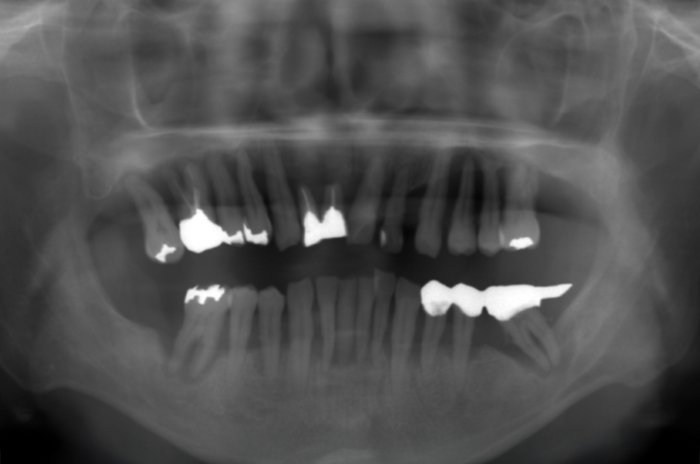

また、レントゲン写真でも歯を支えている骨が吸収していることが明らかで、噛む力を十分に支えられない状態でした。

このままの状態で歯を残すことは難しく、抜歯が必要と判断しました。

レントゲン写真